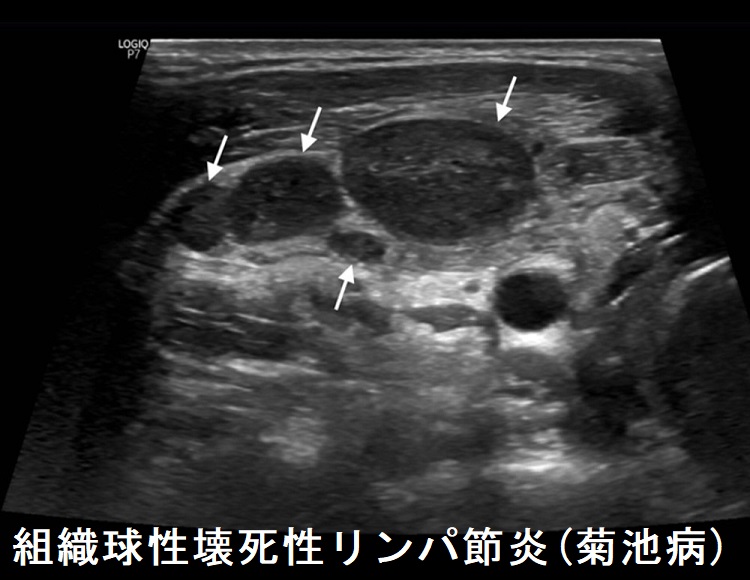

超音波画像診断は通常、医師が推奨する第一選択の画像診断方法です。頸部リンパ節炎や首にあるリンパ節の腫れの診断に役立ちます。